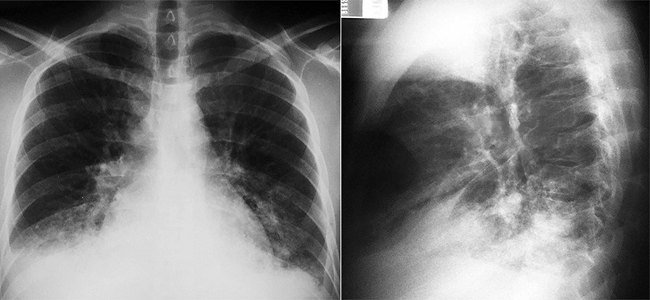

The physical examination revealed an ill-looking patient who was tachypneic, tachycardic, and febrile (38.3°C), with 120/40 mmHg blood pressure and 86% room air oximetry. His skin, mucosae, and conjunctivae examinations were normal. An auscultation of his heart revealed the presence of an intermittent third heart sound, plus an ejection murmur radiating to the carotids, and a diastolic murmur—the latter two at the base of the heart. Pulmonary auscultation revealed decreased sounds in the right base. The abdominal examination revealed a mildly enlarged liver, and the lower limbs exhibited bilateral edema. Laboratory examinations showed a marked leukocytosis 22,800 leukocytes/mm3 (reference value [RV]: 4.4-11.3 × 103/mm3). There were no other abnormalities in the remaining blood cell count and the biochemical work-up. Urinalysis showed sterile leukocyturia (20,000 leukocytes/mm3). HIV and syphilis serology were negative. The electrocardiogram was normal; the plain thoracic X-ray showed a normal cardiac silhouette and an alveolar space-filling opacity in both inferior pulmonary lobes accompanied by a tiny pleural effusion on the right side (Figure 1). The transthoracic echocardiogram revealed normal-sized cardiac chambers as well as normal septum and posterior wall thickness, preserved systolic function, and aortic valve thickening with marked diastolic reflux. The patient was hospitalized and an empiric antibiotic regimen comprising vancomycin, gentamicin, and ceftriaxone was started because of the suspected diagnosis of acute infective endocarditis. The outcome was unfavorable with severe hypotension and persistent respiratory failure requiring vasoactive drugs infusion and non-invasive respiratory support, which meant that the transesophageal echocardiography could not be performed. On the second day of hospitalization, the patient presented cardiac arrest and was unresponsive to the advanced cardio life support maneuvers. The autopsy was performed after informed consent by the family.